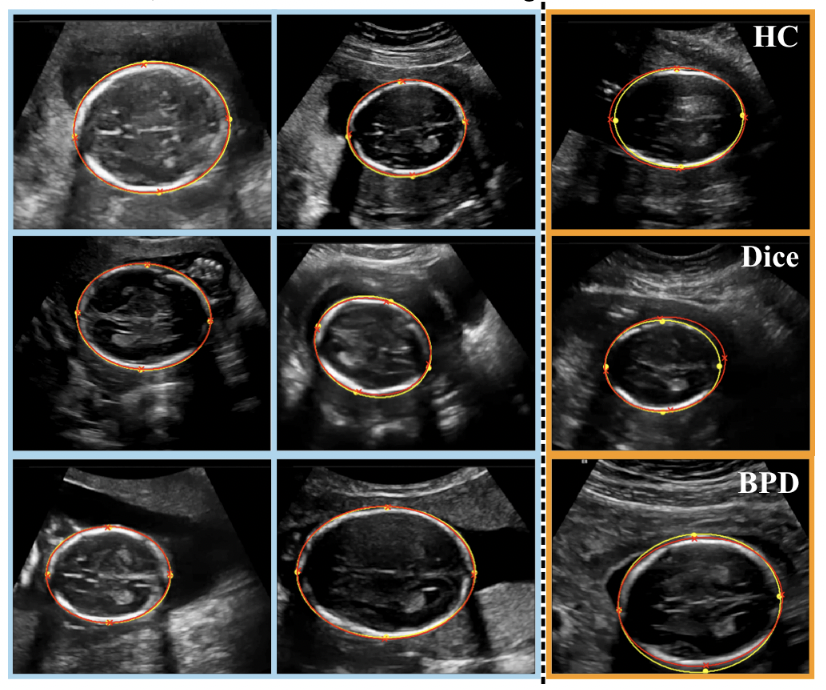

Human-level Performance On Automatic Head Biometrics In Fetal Ultrasound Using Fully Convolutional Neural Networks

Matthew Sinclair, Christian F. Baumgartner, Jacqueline Matthew, Wenjia Bai, Juan Cerrolaza Martinez, Yuanwei Li, Sandra Smith, Caroline L. Knight, Bernhard Kainz, Jo Hajnal, Andrew P. King, Daniel Rueckert

2018 40th Annual International Conference of the IEEE Engineering in Medicine and Biology Society (EMBC), 714-717 (2018)

journal URL

preprint URL